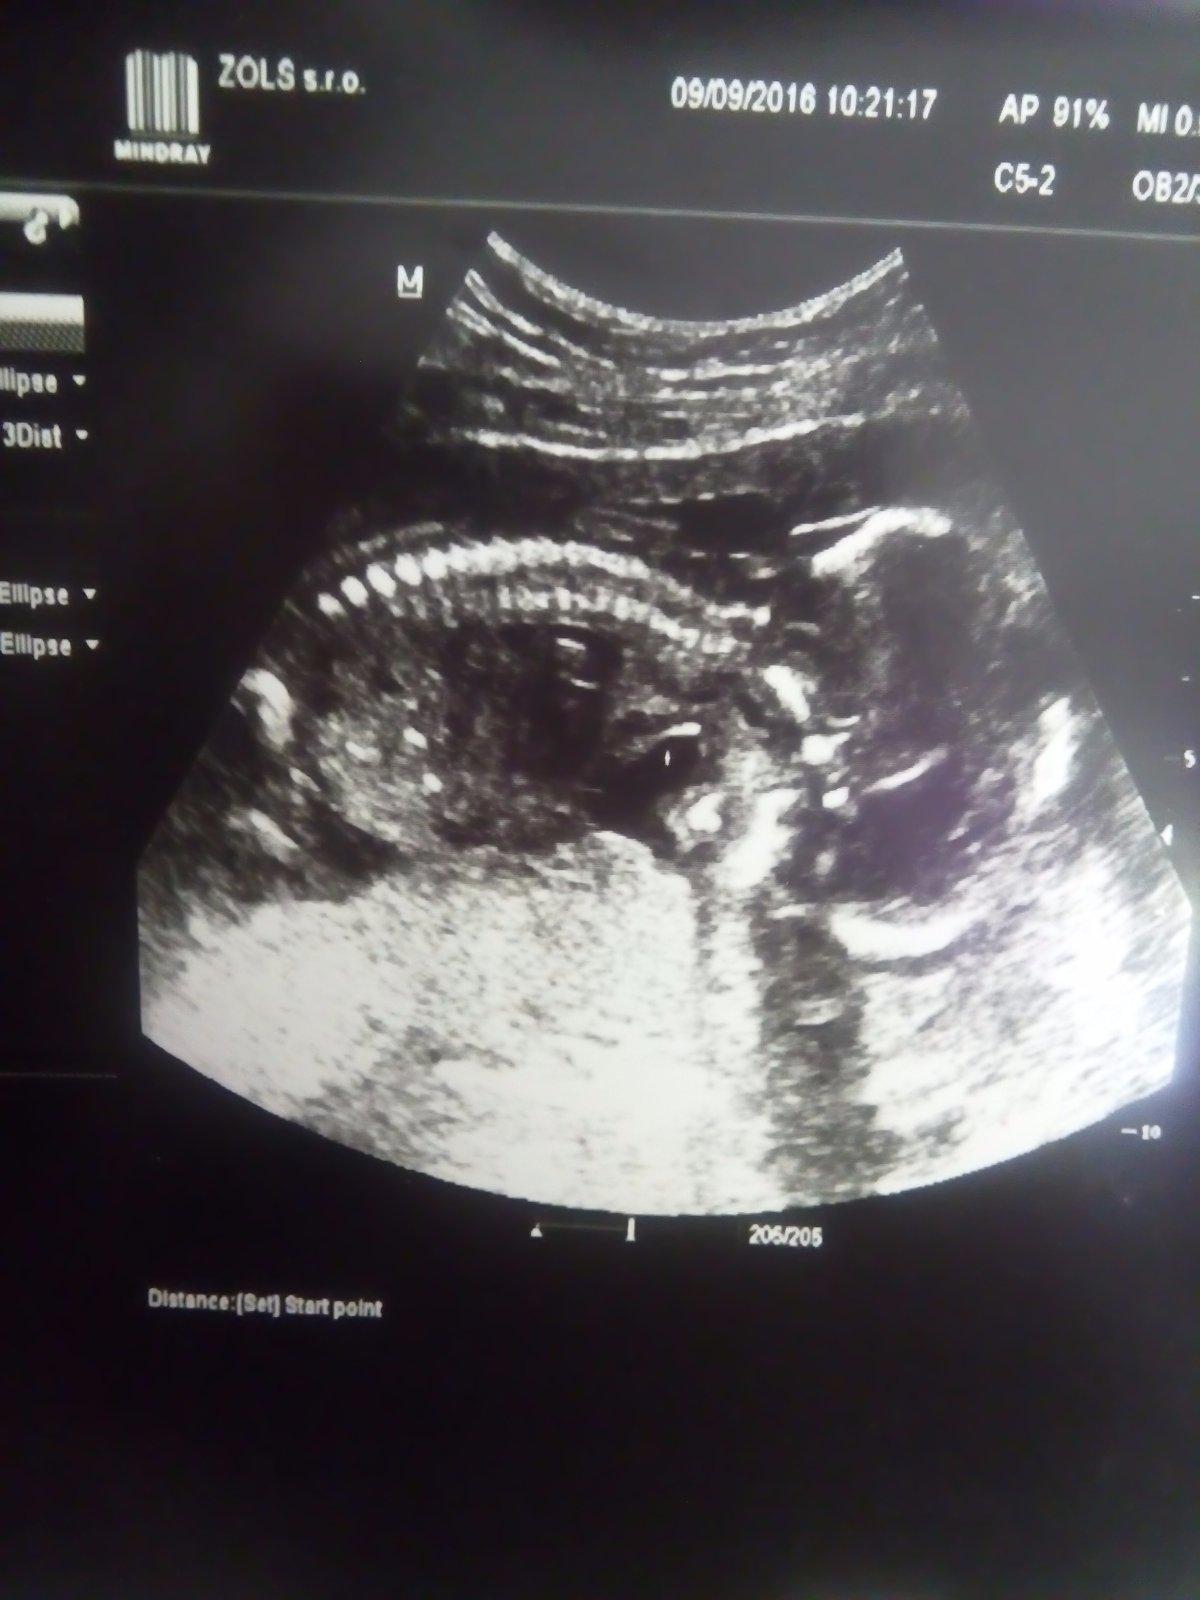

No my mame velkeho tajnostkara 🙂 neukazal sa nam,ach..8tyzdnov som na to cakala a nevieme co cakame,hlavne ze je v poriadku. Len sa mi zda nejake mrňaté,lebo ze len okolo 280g ma a je tak cudne otocene,ze chrbatik nema dole ale hore,takze je tvarou dole :D no nechapem jak sa to dalo škvrňa 🙂

Ahojte no bola som u lekarky a mame krasny chrbat 😡 hlava skovana za placentou a k nam rit a chrbat.. Tvar sme vobec nevideli iba kukla kosti a organy ze to je vsetko v poriadku a na sekundu taku ciarku co vyzerala ze ako susula ze na chlapca tam nic nevidela ale ze potvrdi v utorok ked sa herecka da do povodnej polohy 😂

A mame 419g som 21+6